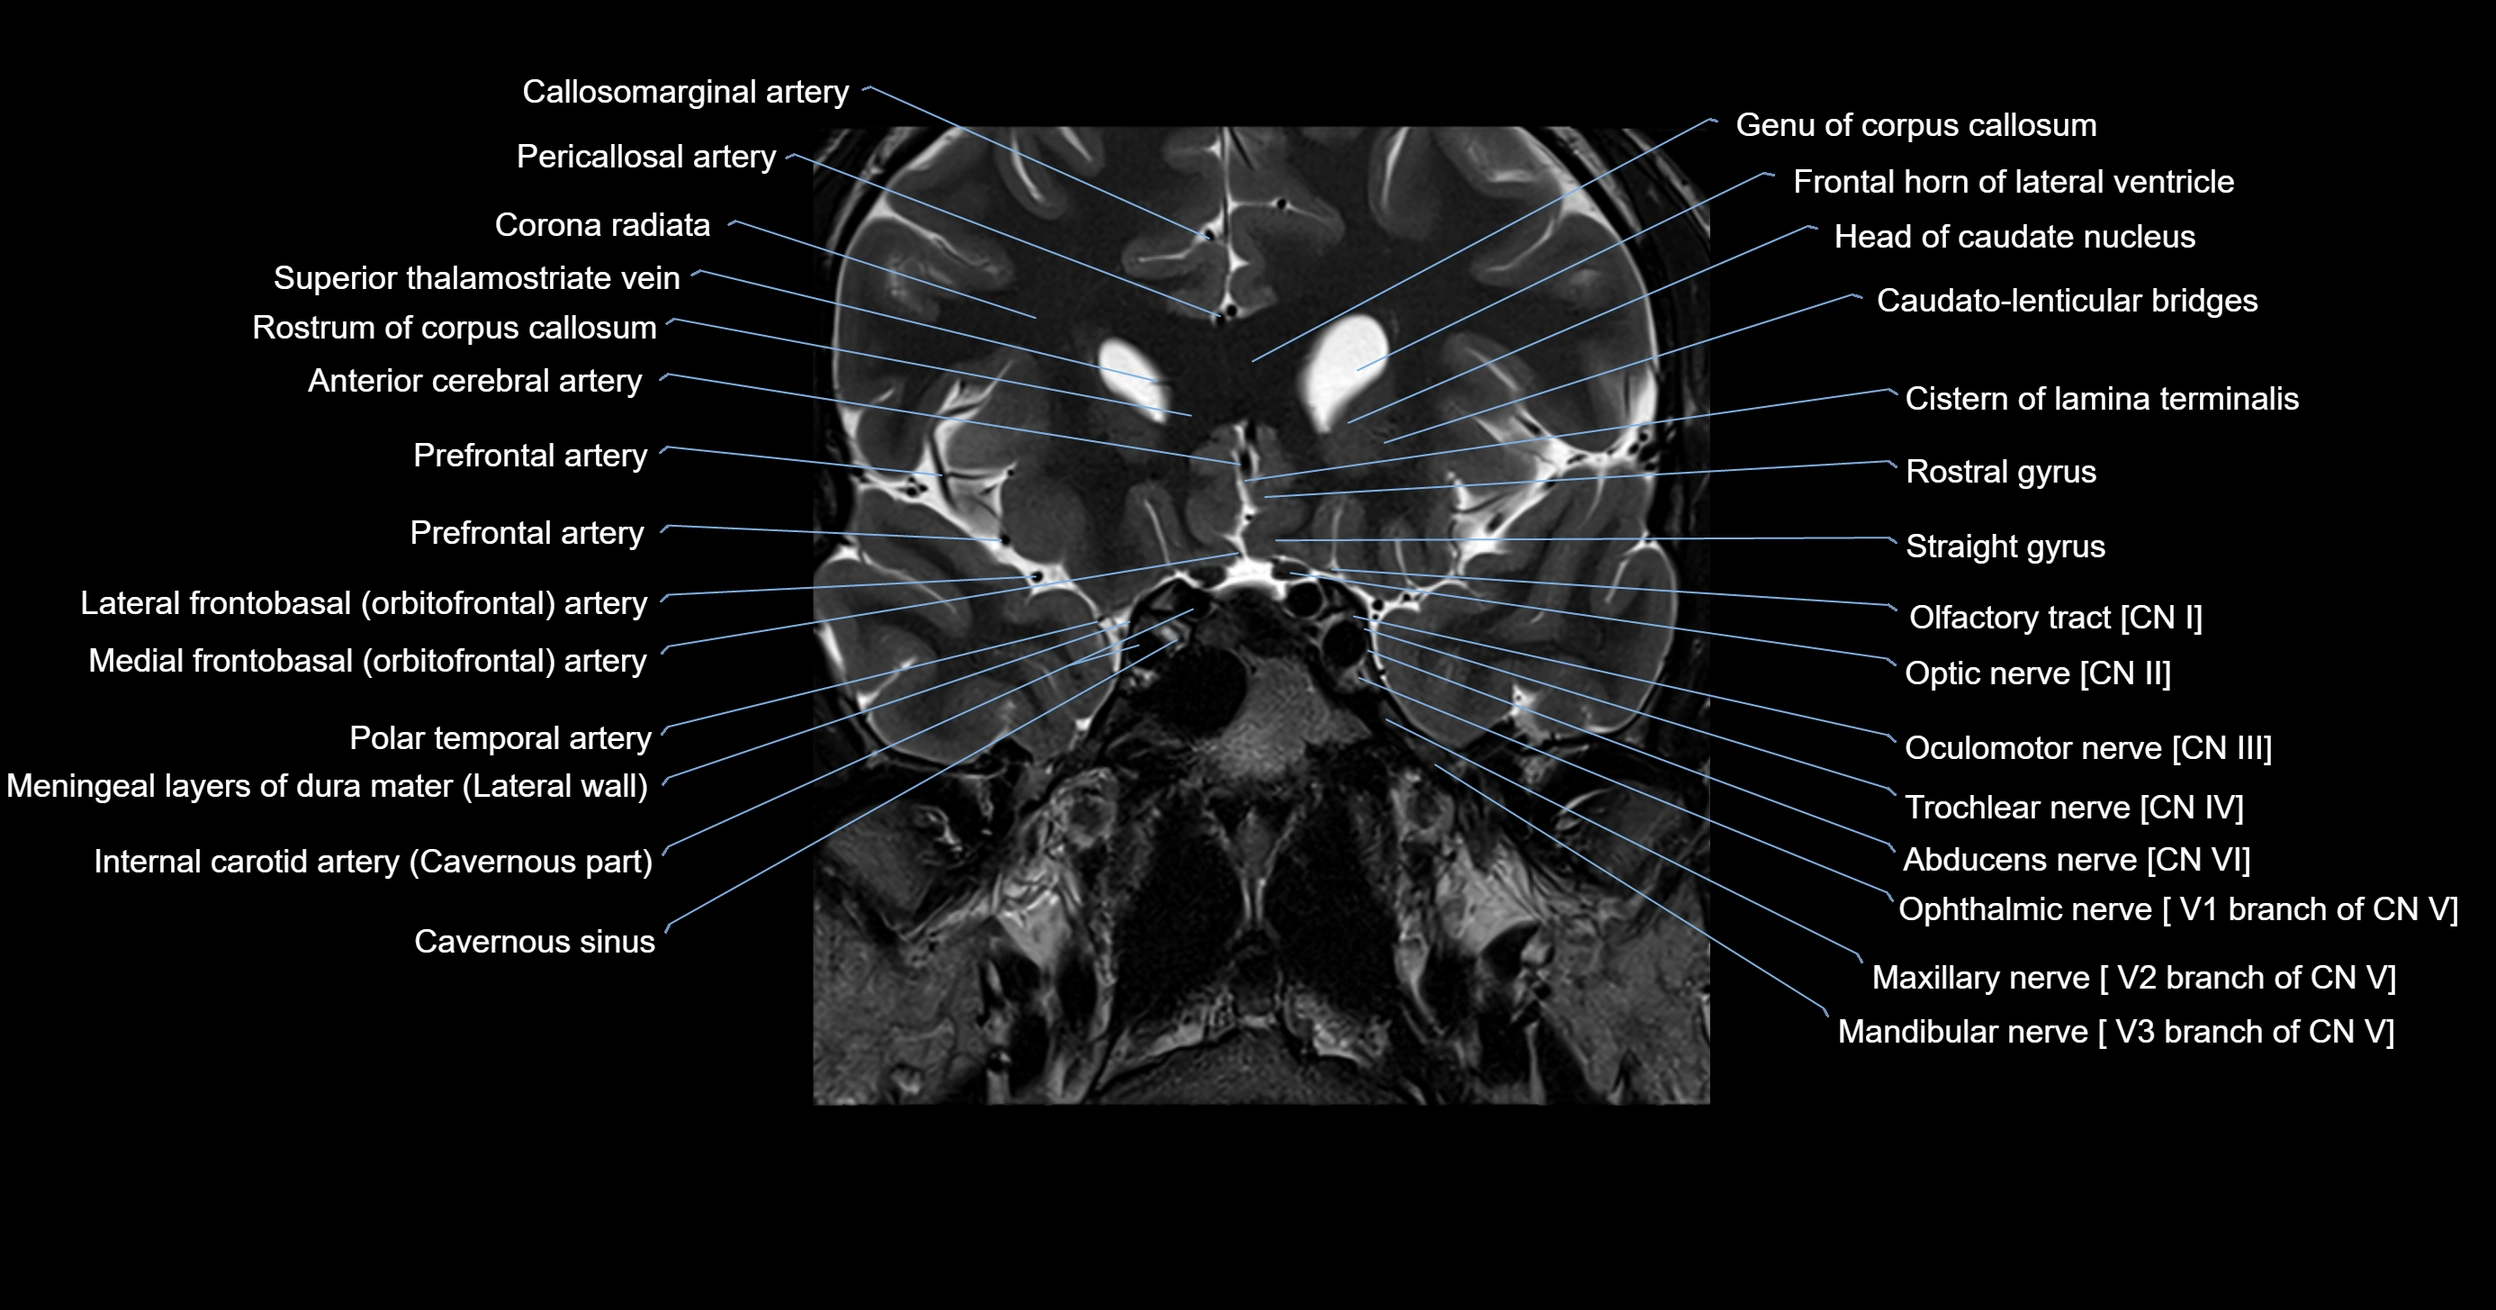

MRI images